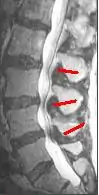

Helpful imaging may include x-rays, CT, CT myelogram, and magnetic resonance imaging (MRI), but MRI is preferred.[1] Abnormal MRI findings may be present in two-thirds of asymptomatic individuals, and imaging findings of spinal stenosis do not correlate well with symptom severity. Therefore, imaging findings must be considered in the context of a patient's history and physical exam when seeking a diagnosis.[2] The evidence for using objective imaging findings to define NC has been conflicting.[12]

Degenerative disc disease (DDD) may trigger the pathogenesis of neurogenic claudication. When intervertebral discs degenerate and change shape in DDD, the normal movements of the spine are interrupted. This results in spinal instability and more degenerative changes in spinal structures including facet joints, ligamentum flavum, and intervertebral discs. These pathologic changes result in narrowing of the vertebral canal and neurovascular compression at the lumbosacral nerve roots.[1][17] The compression of these spinal nerve roots that control sensation and movement in the lower body results in the tingling, pain and weakness NC patients often experience. However, because the severity of symptoms does not correlate well with the degree of stenosis and nerve root compression, a clear understanding of the specific pathogenesis remains challenging.[7]

These changes in blood flow may occur during back extension when shifts in vertebral structures and ligaments narrow the spinal canal and compress the neurovasculature.[15] Compared to a neutral position, extended spines exhibit 15% less cross-sectional area of the intervertebral foramina, and nerve root compression is present one-third of the time.[10] These dynamic changes in the shape of the spinal canal are more pronounced in individuals with spinal stenosis. The amount of narrowing may be 67% in LSS compared to 9% in healthy spines.[1]